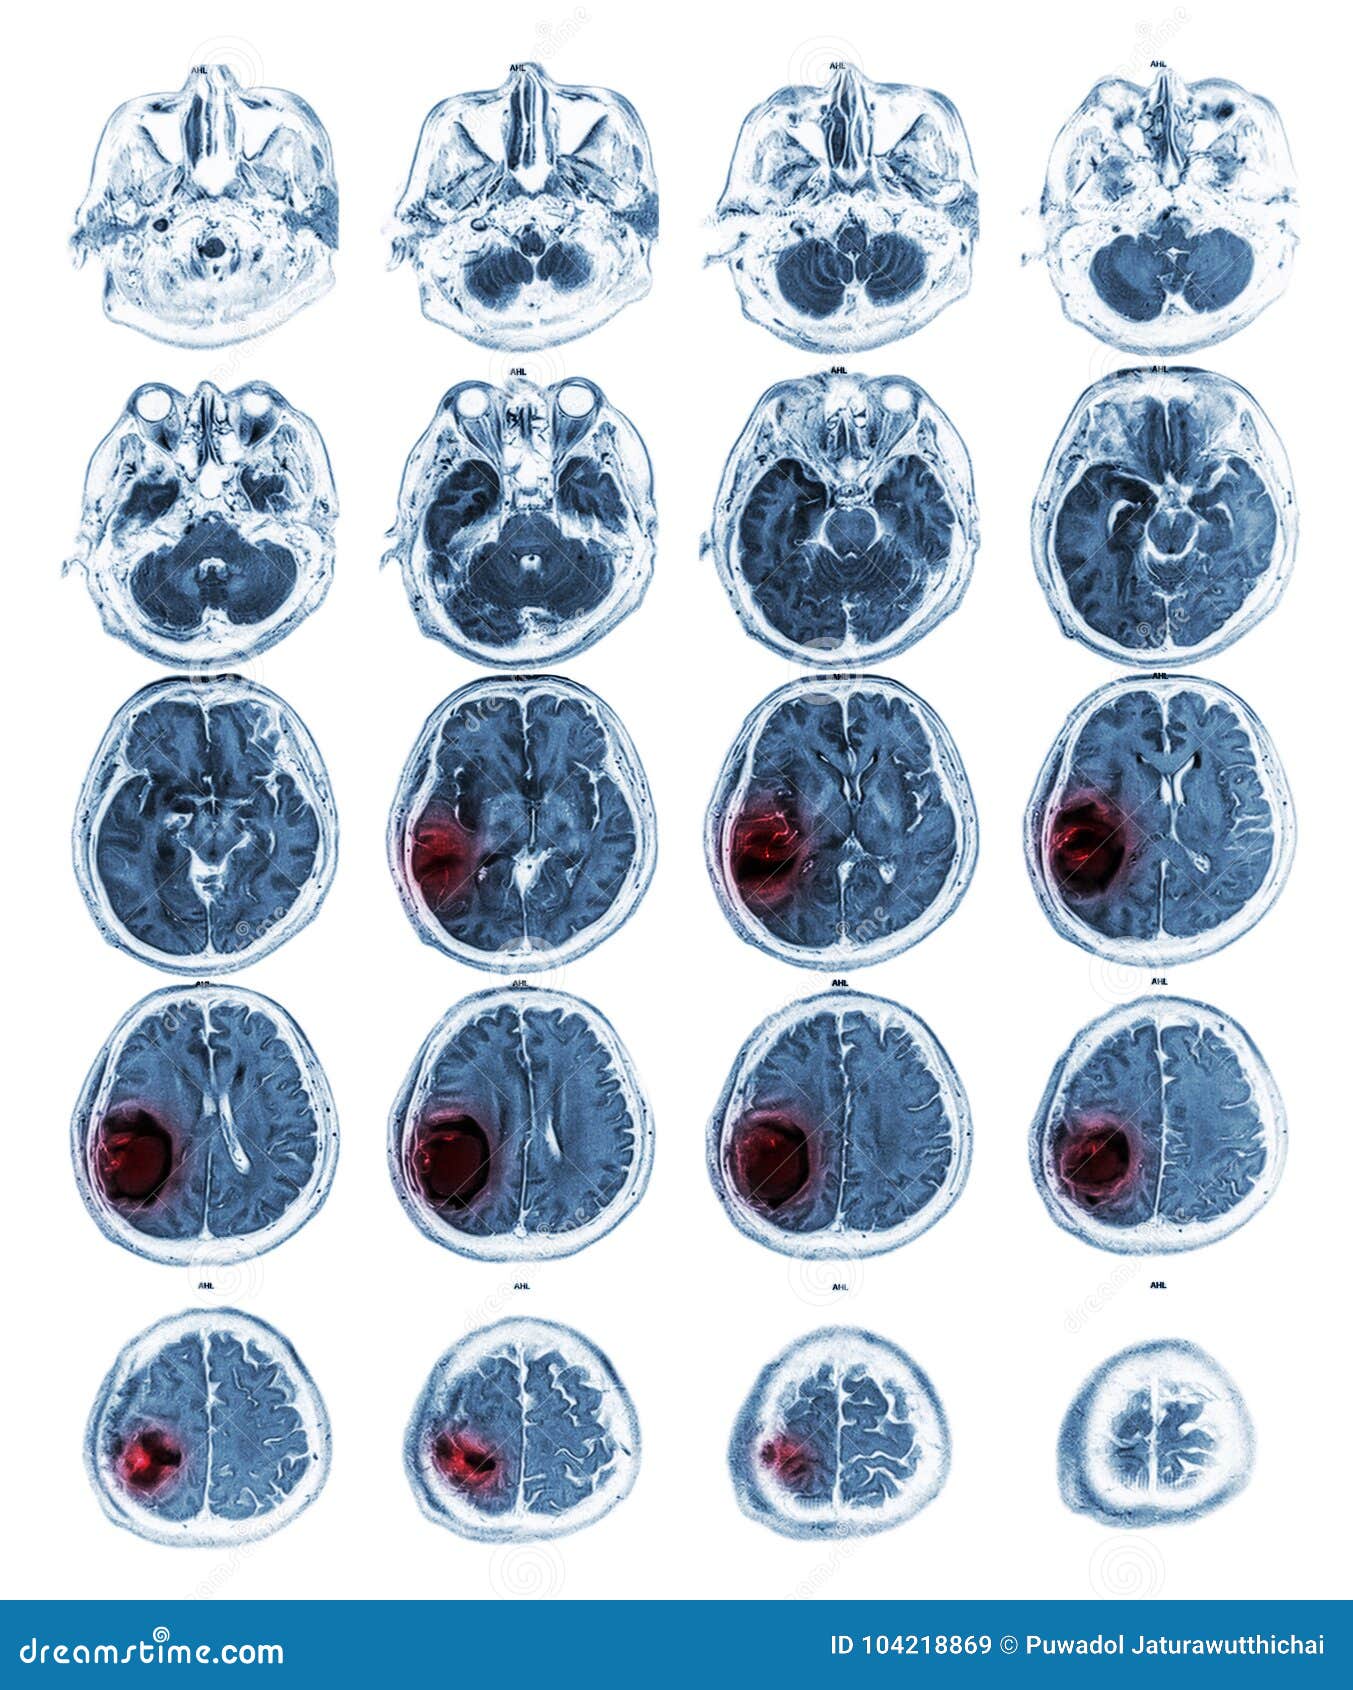

MRI Brain Show Brain Tumor at Right Parietal Lobe Stock Image Image Does Blood Work Show Brain Cancer when brain tumors happen in children, they're likely to be primary brain tumors. If the tumour is affecting your pituitary gland or. In adults, brain tumors are more. brain tumours can affect people of any age, including children, although they tend to be more common in older adults. a malignant brain tumour is a cancerous growth in. Does Blood Work Show Brain Cancer.

MRI brain show brain tumor at right parietal lobe of cerebrum Stock Does Blood Work Show Brain Cancer a malignant brain tumour is a cancerous growth in the brain. If the tumour is affecting your pituitary gland or. Blood tests can also help in assessing some types of brain tumors, and a lumbar puncture may help in diagnosing metastatic (aggressively spreading) tumors in the brain. brain tumours can affect people of any age, including children, although. Does Blood Work Show Brain Cancer.